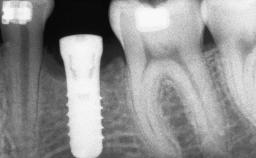

Shell Technique for Horizontal and Vertical Maxillary Bone Augmentation in a Partially Edentulous Patient with Aggressive Periodontal Disease

A 46-year-old woman was referred for treatment whose main complaints were mobility of her fixed partial dentures (right maxilla and left mandible) and periodontal bleeding during function. She also reported having taken systemic antibiotics to treat recurrent swelling in the area of the upper left molars. The patient had not seen a dentist for at least 2 years. She did not smoke and had no history of major systemic disease other than two minor orthopedic procedures some years back. The first-visit examination revealed poor plaque control, tooth mobility, periodontal disease, and a residual dentition widely associated with deep periodontal pockets.

Bone Augmentation Horizontal|Staged|Vertical

Augmentation Materials Autogenous chips|Autogenous block(s)|Xenogenous

Bone Volume Deficient vertically or deficient vertically AND horizontally